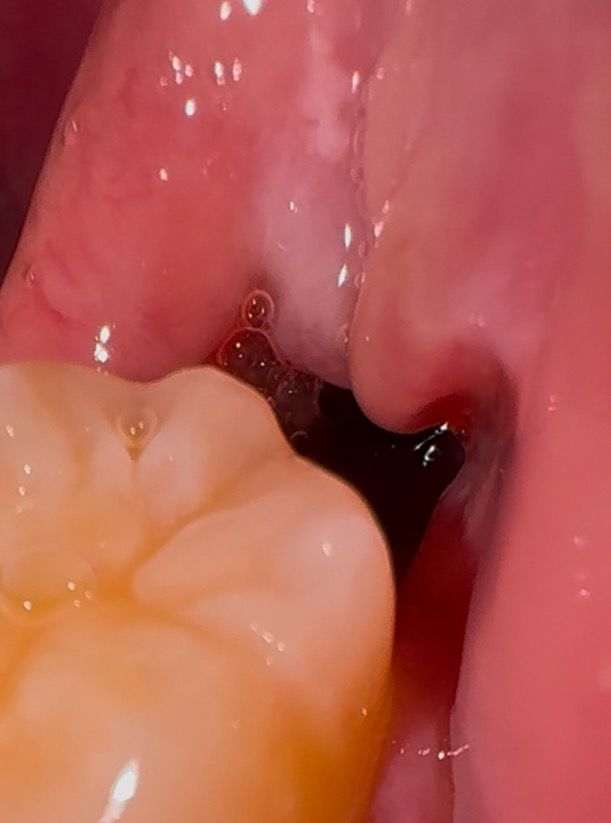

사랑니 발치 10일차 물?침?같은게 계속 나옵니다

매복 사랑니 발치한지 10일차고 저번주 금요일에 실밥 풀었는데, 사랑니 발치한 자리에서 물같은게 계속 나옵니다.

통증은 없고 피는 아닌거같은데 문제가 있는걸까요?

• 1번 째 사진

사랑니를 발치한부위의 혈병이 형성되지 읺으면 내부의 잇몸이 잘 차오르지 않게 되어 빈공간이 클 수 있습니다 이런 빈공간에는 이물질이나 남아있던 타액이 흘러 나올수 있습니다.

이런 빈공간은 대부분 시간이 지나면서 차오르게 되기 때문에 해당 부위를 자극하지 않는 것이 좋습니다

사진상에도 괜찮아보이고 통증도 없고 피가 나는 것도 아니라면 크게 문제가 될 것은 없어보입니다.

아직은 잇몸이 다 아물지 않아서 그러는거니 너무 걱정하지마시고 음식물만 남지 않도록 관리만해주시면될것같습니다.

실밥 풀때 치과에서 소독을 해주는데 그 소독물이 발치 부위 구멍에 잔류하다가 조금씩 나오는게 아닐까 추측됩니다